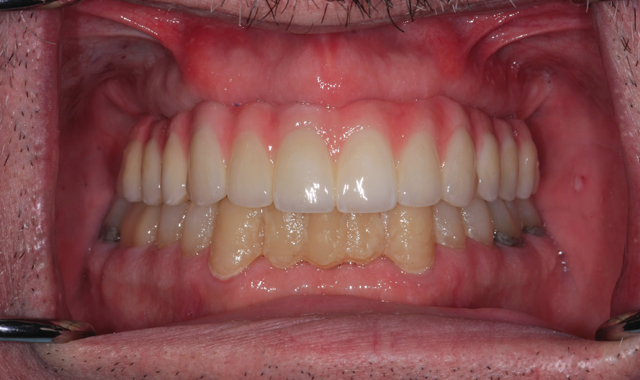

Fig. 16 Try-in the mouth

Final, upside down view of the six implant units (Fig. 16) follow.